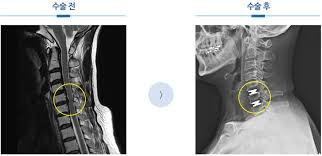

https://adsense.google.com/adsense/u/1/pub-9161951367286286/myads/sites/preview?url=notion6988.tistory.com 🦴 '뼈를 깎는 아픔' 없이 척추 수술 새 길 열었다